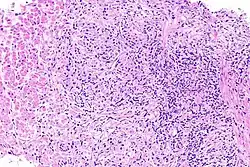

Prostatitida je zánět předstojné žlázy, spíše známé pod názvem prostata. Jedná se o nejčastější urologický problém mužů do 50 let.[1] Mezi její symptomy patří horečka, zimnice, dysurie či sexuální poruchy. K léčbě jsou indikována antibiotika.[1]